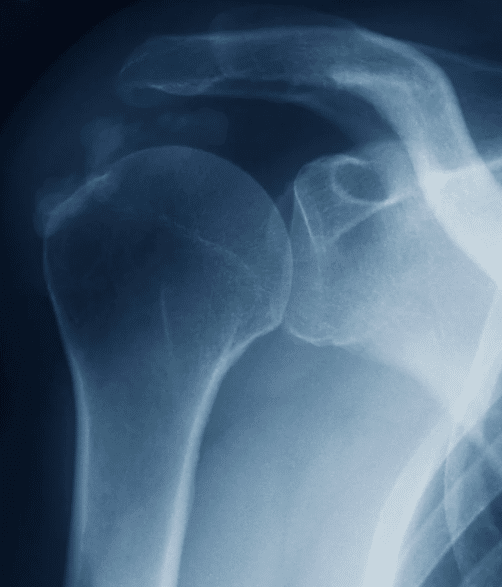

El hombro es una de las articulaciones más móviles del cuerpo humano. Gracias a él podemos levantar los brazos, girar, empujar y realizar cientos de movimientos diarios. Pero justamente esa movilidad lo hace vulnerable a lesiones, siendo la tendinitis una de las más comunes.

Se trata de una inflamación de los tendones que rodean la articulación, y que puede afectar tanto a deportistas como a trabajadores manuales o personas que realizan movimientos repetitivos en su día a día. Aunque al inicio parece un dolor pasajero, si no se trata a tiempo puede transformarse en una molestia crónica y limitante.